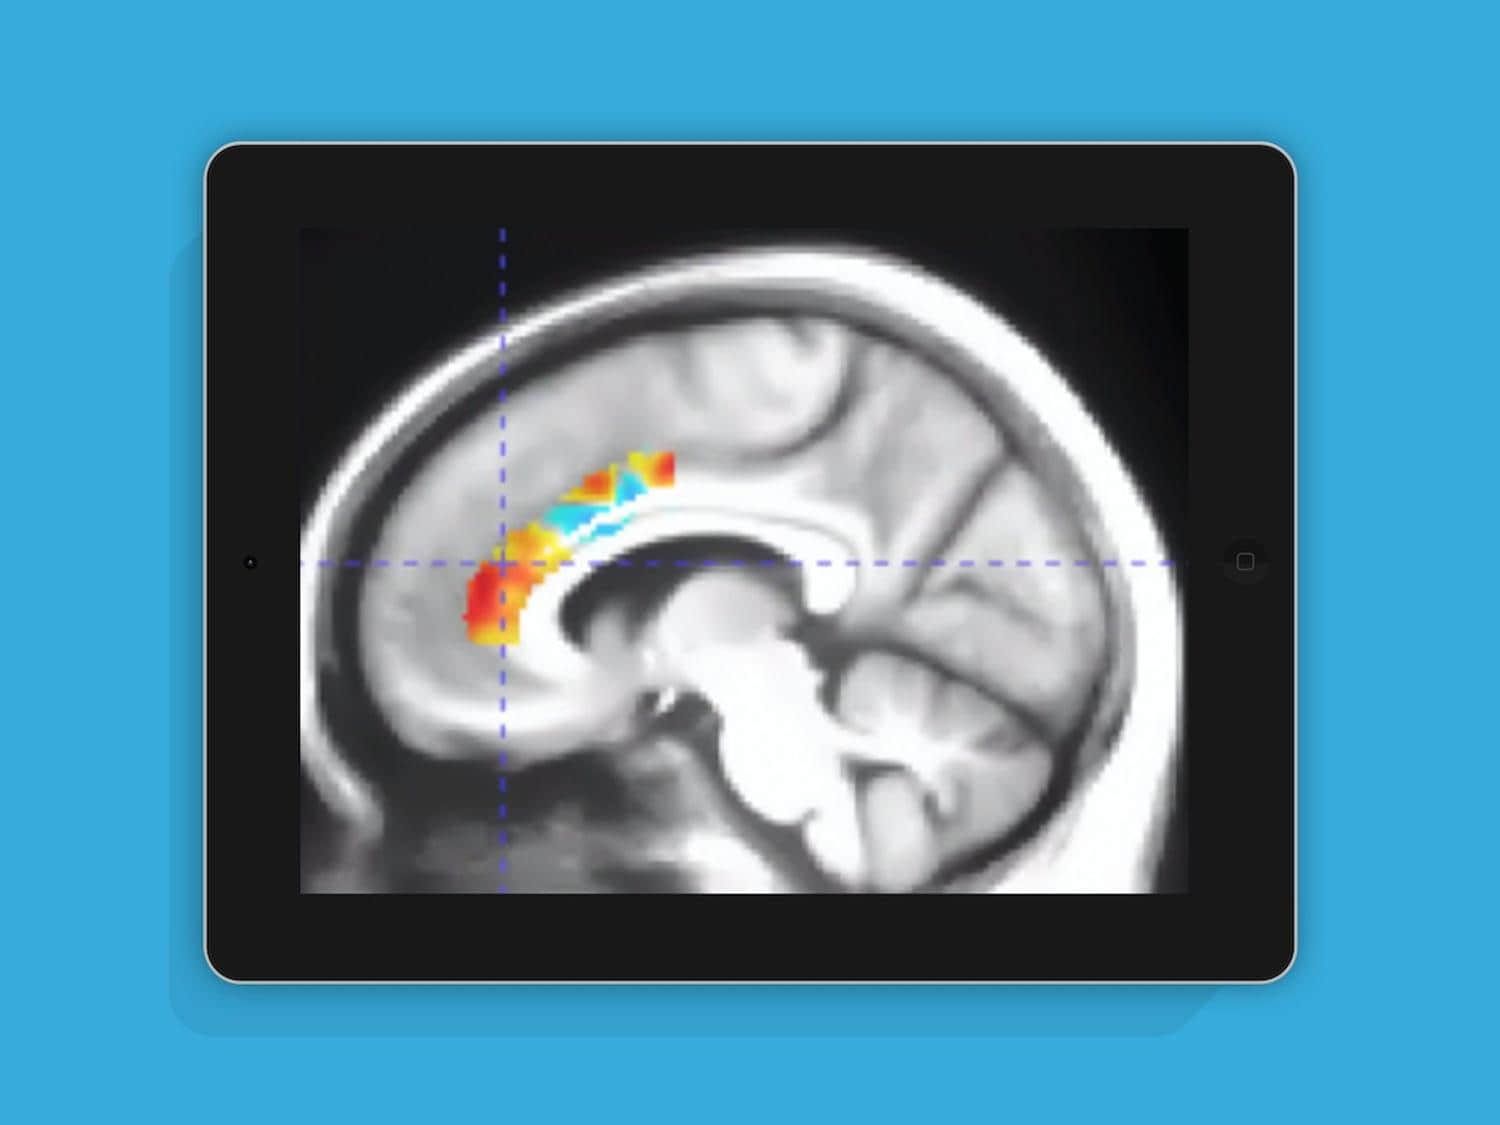

受试者在10周内累计完成35小时家庭训练,最终82名参与者完成全程。通过追踪与乙酰胆碱神经递质特异性结合的[18F]氟乙氧基苯并维沙米科尔示踪剂,正电子发射断层扫描数据显示:仅脑力训练组的前扣带皮层出现2.3%的显著结合率提升。

值得注意的是,该指标通常随年龄增长以每10年2.5%的速度递减。这意味着在易受衰老影响的脑区域,10周训练可能逆转约10年的生理老化。